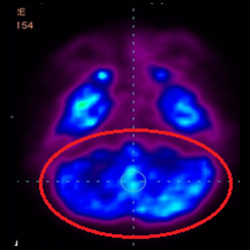

干細胞治療腦癱后改善的客觀放射學證據

細胞治療前 PET CT 掃描顯示神經組織中的藍/黑色區域,表明腦癱引起的大腦損傷。

細胞治療后,藍色和黑色區域減少,并且看到更活躍的區域。這表明損傷減少并改善了大腦功能。

這證明細胞療法是治療腦癱兒童安全有效的方法。細胞療法可以更新大腦損傷的核心,并且可以通過 PET CT 掃描來監測大腦的改善情況。這些細胞療法與標準治療一起促進腦癱兒童的生長和改善。